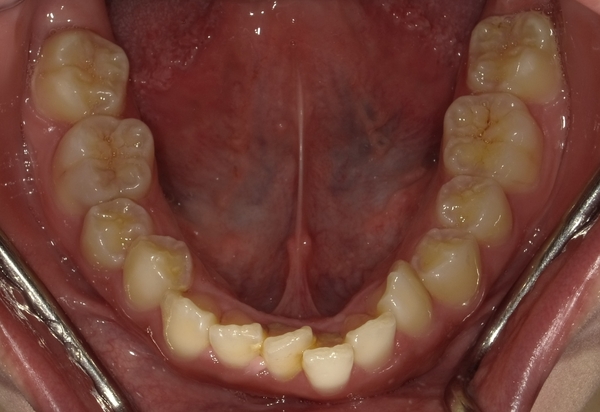

ガタガタとした歯並びや八重歯(叢生)CASE53